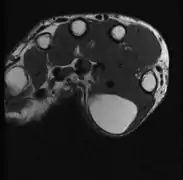

A physical exam is typically the easiest way to diagnose it. Rarely, a tissue biopsy or imaging may be required. The imaging modality of choice is magnetic resonance imaging (MRI) because it has superior sensitivity of distinguishing it from liposarcoma as well as mapping the surrounding anatomy.[22]

Medical ultrasonography of a lipoma in the thenar eminence: It is hyperechoic compared to adjacent muscle, and relatively well-defined, with miniature hyperechoic lines.[23]

MRI showing lipoma of the arm